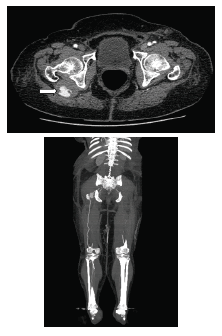

En la arteriografía (figura 1) se evidenció: una arteria ciática persistente derecha permeable, con degeneración aneurismática proximal, con recorrido por el muslo sin lesiones y unión con la arteria poplítea en su segunda porción; trombos suboclusivos en dicho aneurisma; ateromatosis de la arteria femoral superficial derecha en su tercio medio y distal, con estenosis crítica en su unión con la arteria poplítea, y llegada distal a este sitio de la arteria ciática persistente. Las arterias ilíacas y femorales izquierdas fueron normales. Se observaron trombos oclusivos en la arteria femoral superficial derecha distal, en la primera porción de la arteria poplítea, y en las arterias tibial posterior y peronea.

Se consideró que la causa de la isquemia aguda fue la embolia desde el aneurisma de la arteria ciática persistente y que la mayoría del flujo de la extremidad estaba dado por dicha arteria anómala. Con el fin de planear la corrección del aneurisma de la arteria ciática persistente, para evitar eventos isquémicos posteriores, se practicó una angiotomografía de los miembros inferiores (figura 2).